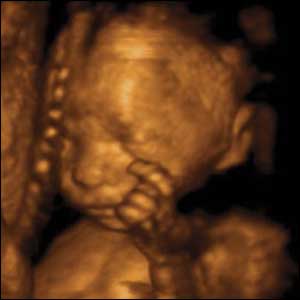

15 weeks gestation, 11cm crown to rump

5 of 10

This baby's brain has developed sufficiently to enable him apparently to sense the other parts of his body. He can bring his fingertips together so they touch.